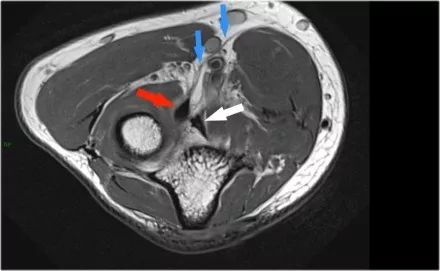

下面的图像,请注意,前束是完整的,并牢固地附着在崇高的结节上(黄色箭头)。在接下来的两张图像上,有一些软组织水肿,后面有更多异常信号(红色箭头)。所以我们怀疑后束的病理学。现在你记得轴向图像可能会有所帮助。

在下面轴向图像上,我们很好地看到前束是o.k. (红色箭头)。它旁边只有一些水肿。

然而,后束不是o.k,有一部分撕裂。这种情况我们偶尔会在投掷运动员中看到,前束完整,肘部不稳定。他们以某种方式撕裂了他们的后束,导致疼痛。他们不需要手术,但它仍然可能让他们在游戏中停留很长一段时间。